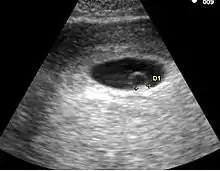

- Le premier signe échographique d'une grossesse est la visualisation d'un sac ovulaire. Il est visible entre 4 semaines et 1 jour et 4 semaines et 3 jours; Il mesure alors 2 à 3 mm. L'utilisation de la voie endovaginale est souvent nécessaire pour le voir. Le sac ovulaire a l'aspect d'une petite tache noire, excentrée par rapport à la cavité utérine, correspondant à la cavité chorionique entourée d'une couronne d'échogénéicité forte : le trophoblaste.

- À cinq semaines, le sac ovulaire mesure 5 mm. Il est quasiment toujours visible lors de l'échographie par voie abdominale. Il est parfois difficile d'affirmer la localisation intra-utérine de la grossesse en raison de l'aspect de pseudo-sac gestationnel décrit au cours des grossesses extra-utérines. Seuls deux signes sont pathognomoniques de la grossesse intra-utérine

- L'aspect en double cercle du sac (double decidual sac sign) correspondant une couronne hyper-échogène interne en rapport avec la trophoblaste et une couronne hypo-échogène externe en rapport avec la transformation gravidique de l'endomètre

- La visualisation de la vésicule vitelline qui affirme définitivement le caractère ovulaire de l'image échographique.

- La visualisation de la vésicule vitelline est un élément essentiel pour affirmer le caractère ovulaire de l'image et l'évolutivité de la grossesse. Embryologiquement, la vésicule vitelline visualisée correspond à la seconde vésicule vitelline. La vésicule vitelline est toujours visible à 5 semaines et 5 jours par voie endovaginale. Le sac ovulaire mesure en moyenne 8 mm. Par voie abdominale, elle est toujours visible à 7 semaines (le sac ovulaire mesure en moyenne 20 mm). Le diamètre de la vésicule vitelline augmente de 5 à 10 semaines pour atteindre 5 à 6 mm.